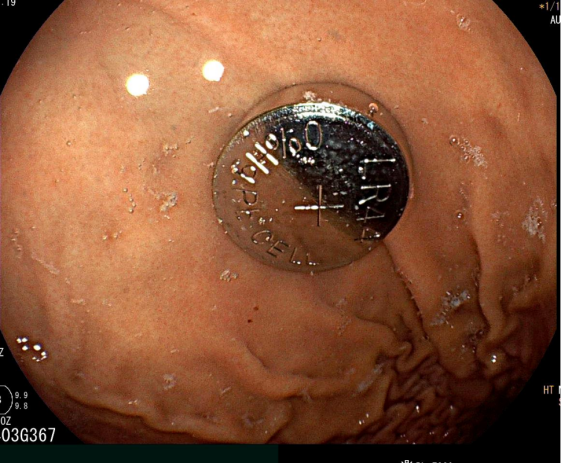

在麻醉团队的密切配合下,消化内科医师将内镜经口缓慢送入,精准定位异物后,以网篮稳妥套住电池,并平稳完整地将其取出。术后再次进镜观察,确认食管及胃黏膜情况良好,未见明显损伤、活动性出血或穿孔迹象。

整个手术过程顺利、耗时较短。取出电池后,患儿被安全送入病房进行后续观察。随着孩子转危为安,家属焦虑的情绪也逐渐平复。

(术后取出的纽扣电池)